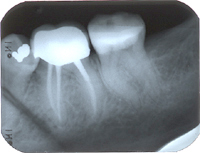

Gelingt es, die drei Ziele (schmerzfrei, entzündungsfrei, keimfrei) mittels der Wurzelbehandlung zu erreichen, werden die Zahngranulome innerhalb von sechs Monaten automatisch verschwinden und es bildet sich wieder gesunder Knochen um die Wurzelspitzen.

In Abb. 2 ist das Röntgenbild 22 Jahre nach korrekter Wurzelbehandlung mit dem nun überkronten Zahn zu sehen. Der Knochen um die Wurzelspitzen ist entzündungsfrei gesund.